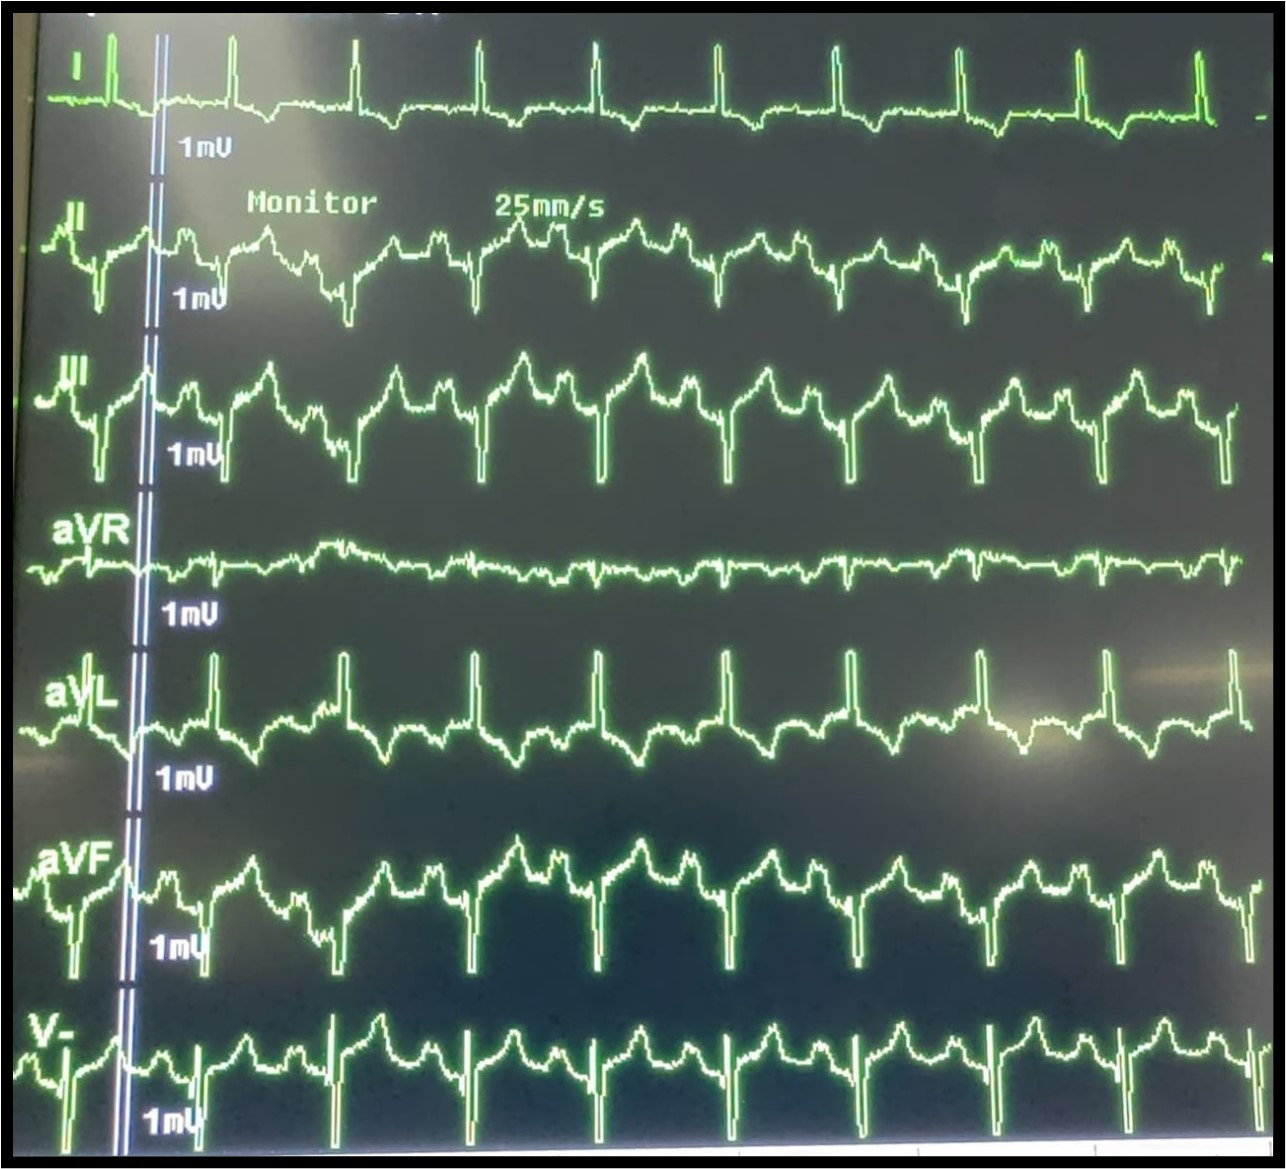

Electrocardiogram

The electrocardiogram (Figure 4) showed left axis deviation, absence of lateral Q waves, and presence of Q waves in V1, consistent with ventricular inversion as seen in CCTGA. A prolonged PR interval suggests first-degree AV block, and features of right ventricular hypertrophy are also present, correlating with the patient’s severe pulmonary stenosis.

Figure 4

The ECG findings in this patient are characteristic of CCTGA. Left axis deviation reflects the inverted position of the ventricles. The absence of lateral Q waves and presence of Q waves in V1 result from the ventricular inversion, as the septal activation sequence is reversed. The first-degree AV block (prolonged PR interval) is common in CCTGA due to the elongated and abnormal course of the conduction system through the heart. Studies show that approximately 2% of CCTGA patients develop progressive conduction disorders annually, with many eventually requiring permanent pacemaker implantation [6].